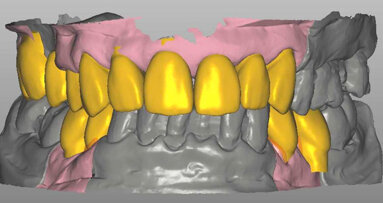

Alla visita del CTU le condizioni cliniche sono peggiori di quelle oggettivate (Figg. 1-4) alla fine del rapporto. Il riconoscimento di concorrenza di cause porta ad accollare a YZ solo parte dei danni rilevati (danno biologico 1% e ITP al 10% per 50 giorni), ma l’inadempimento fa riconoscere anche l’obbligo di rendere quanto percepito per prestazioni inutili e non indicate. Dovrà quindi restituire di tasca propria competenze per almeno 10.000 euro oltre alla franchigia prevista dal contratto di polizza in materia di risarcimento e alle spese legali. Nelle incaute promesse il Giudice riconosce, inoltre, un grosso vizio di consenso.

L’estetica in odontoiatria è un gioco di equilibri tra denti, tessuti molli, labbra, viso e persone.